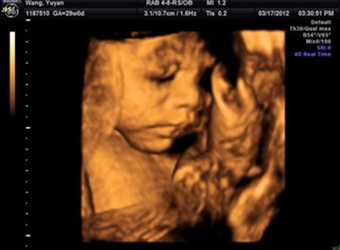

四维彩超是目前比较流行的孕检之一,四维能对胎儿头面部立体成像,可清晰显示胎儿的状态,网上很多四维是女孩但是却生了男孩的案例,那么四维女孩翻盘几率大吗…

四维彩超是实时的立体成像,在孕检的时候主要是帮助筛查胎儿的畸形,四维由于清晰度高也有用来判断胎儿男女,那么四维看是男孩有可能是女孩吗,四维男翻女的几…

四维彩超的报告中有很多的指标,网上也流传了很多通过报告单看男孩女孩的方法,那么四维胎儿双侧肾盂无分离是男是女,5个月四维如何看男女呢?更多关于生男生…

很多网上的宝妈都有看到这个情况,那就是做了四维彩超是男孩,但是却生了女孩,很多宝妈担心四维做的是男宝有可能翻盘吗,为什么四维男宝变女宝?更多关于生男…

网上有一种说法是,在做四维彩超的时候,如果是女宝宝是比较不容易配合的,如果是男宝宝更容易通过,那么是不是四维女宝更容易配合呢,四维女宝特征有哪些?更…

做四维彩超的时候,需要宝宝在肚子里动起来,有配合效果才是最好的,网上说做四维的时候不配合的都是女宝宝,那么这种说法是真的吗,四维是女宝还会翻盘吗?更…

很多宝妈都有在网上看到,做四维彩超的结果是女孩,但是最后生下的是男孩的案例,那么四维看是女孩最后会是男孩吗,女孩翻盘男孩的几率大不大?更多关于生男生…

网上流传着很多宝妈做四维彩超检查,医生说是男孩,但是结果生出来是女孩的案例,那么四维彩超男孩翻盘实例有哪些,为什么四维是男孩结果生女孩?更多关于生男…